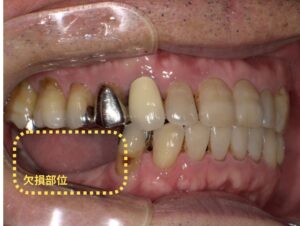

世界的信頼性の高いインプラント、培われた知識・技術、先進デジタル技術により、安全性と正確性を高めたインプラント治療を実施。麻酔科医とも提携し、痛みや不安にも配慮しています。